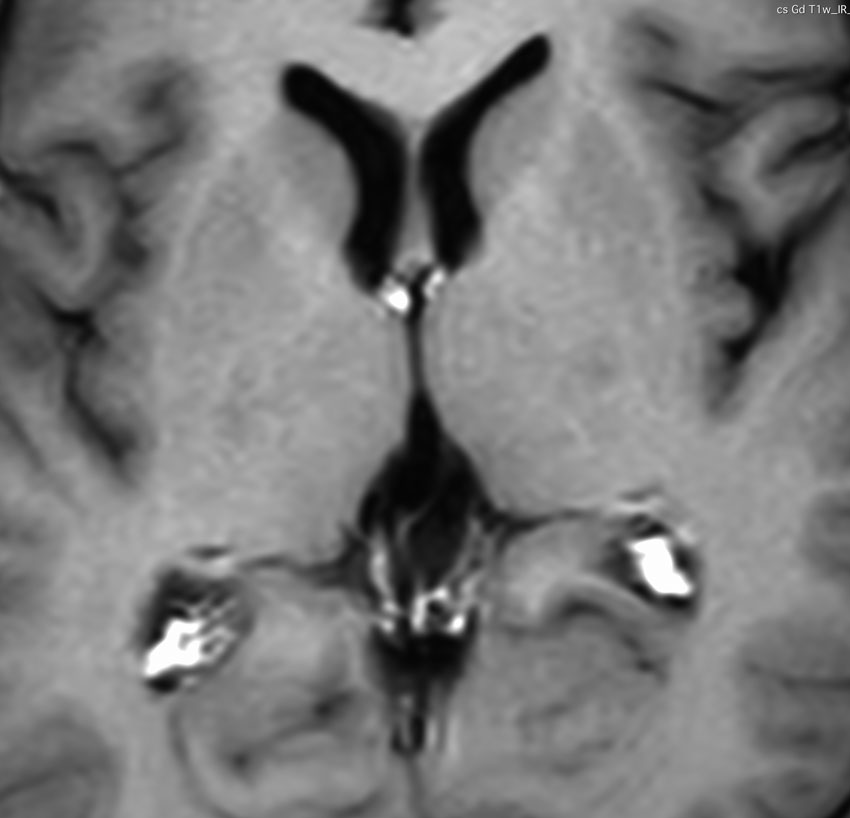

この例は古いので第3脳室開窓術 ETV をしていません。左はICE化学療法前。中央は9日後。右は25日後です。閉塞性水頭症があっても1週間くらいで中脳水道が通って水頭症は改善します。ジャーミノーマであれば,ICE化学療法1コースでかなり縮小するはずです。このような顕著な効果がない時には,逆にジャーミノーマ以外の胚細胞腫瘍が混在していると考えた方がいいでしょう。多くは奇形腫の混在です。

2000年頃の例です。閉塞性水頭症を併発する松果体部germinoma:左のMRIは発症時のものです。定位的生検術で確定診断して脳室ドレナージを留置しました。1コースのICE化学療法直後,生検術から6日目のMRI(中央)では腫瘍はほぼ消失し,水頭症は改善したのでドレナージを抜去しました。4コースの化学療法後(右側)に24Gyの全脳室照射を加えました。

松果体ジャーミノーマは両側視床に浸潤して視床浮腫を生じます。真ん中に第3脳室後半部の割れ目が残っているのが特徴的な所見です。ミッキーマウスの耳みたいになります。かなり特異的な所見であり診断に有用です。右下は治療後です。